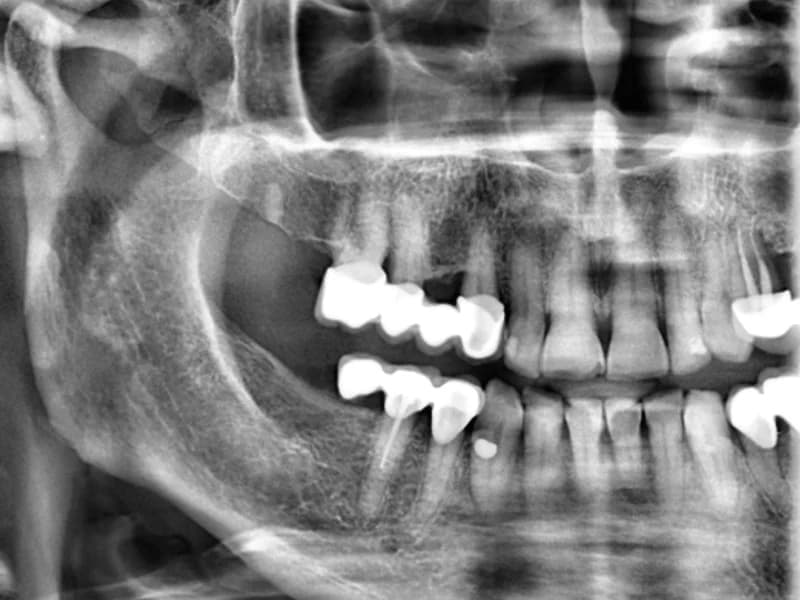

Snimanje digitalnih ortopana, pojedinačnih zuba, sinusa i temporomandibularnog zgloba u Vukovaru.

Galerija